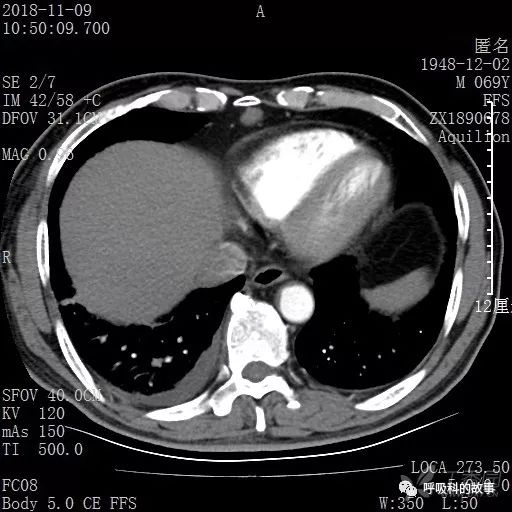

胸部增强CT示右肺门占位伴远端阻塞性肺炎,纵膈、右肺门、右侧颈根部、右侧腋下及肝门部肿大淋巴结。两侧胸腔少量积液。

肺窗CT